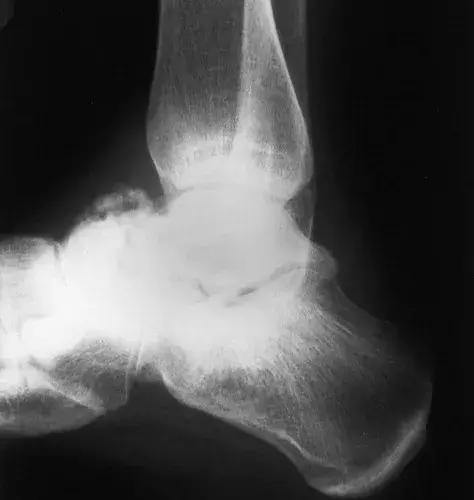

图17:42岁男性糖尿病人,踝关节和后足的神经性骨关节病。侧位X线片显示胫骨远端破坏吸收,并且具有类似于手术截肢的尖锐边缘。 距骨圆顶被吸收。 存在硬化,并且不再能够识别距下关节(箭头)。